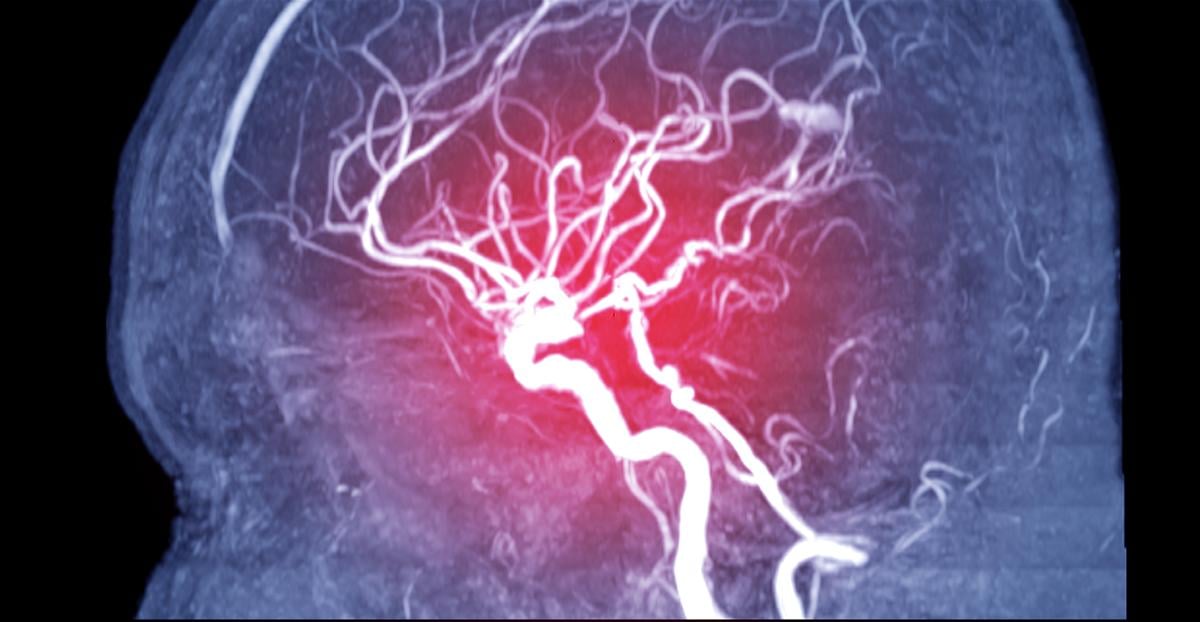

WEDNESDAY, Oct. 2, 2024 (HealthDay News) -- Patients who lose the use of their hands and arms after a stroke or traumatic brain injury could regain some function through deep brain stimulation (DBS), new research demonstrates.

DBS involves surgical placement of electrodes to deliver electrical impulses to areas of the brain regulating specific activity. It is often used to treat control movement problems associated with Parkinson's disease.

The team proposed using DBS to stimulate a structure deep within the brain called the motor thalmus, a key hub of movement control. Because this had never been done before, they first tested it in monkeys, which have the same links as people between the motor cortex and muscles.